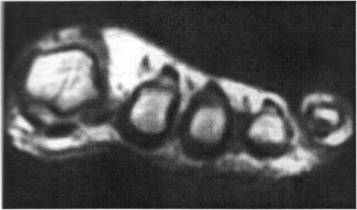

Figura 38. IRM, sectiune axiala TISE la nivelul metatarsienelor. Nevrom Morton: formatiune dezvolta in spatiul 3-4 interosos cu aspect „in clepsidra' si semnal hipointens TI. Formatiunea are dimensiuni centimetrice, si nu modifica diafizele invecinate ale metatarsienelor.